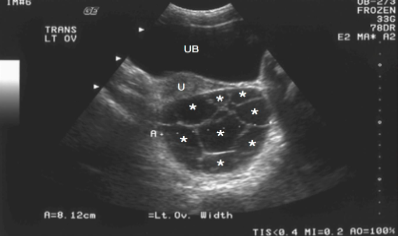

What is this an image of? And how do you know?

Complex cyst bc there are multiple loculations/compartments